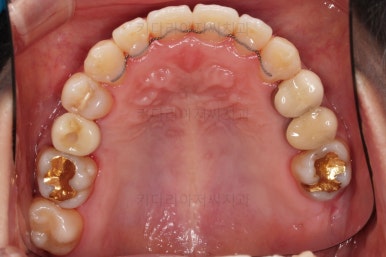

초진 시, 입안의 모습이에요.

결손부위가 눈에 띄고요.

결손부위가 양쪽에 있다보니 윗니 중간에 틈새가 벌어졌네요.

뒤쪽의 빈공간으로 치아들이 도미노처럼 쓰러져서 그렇습니다.

따라서 치아를 상실하게 되면 임플란트 등 적절한 조치를 즉시 취해주는 것이 가장 좋습니다.

앞니의 약간의 틈새, 약간의 삐뚤어짐, 약간의 중앙선 틀어짐 등 심하진 않으나 약간씩의 문제점들이 있네요.